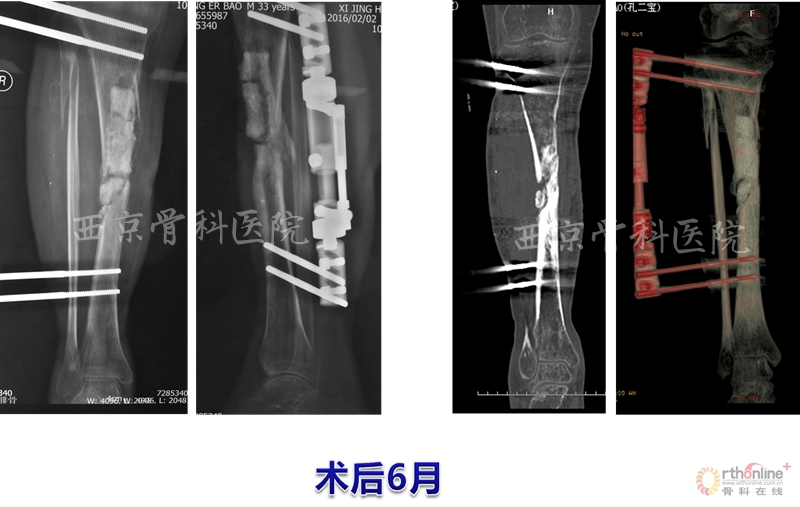

术后,他们按照组织工程再生骨临床转化应用方案定期进行血液指标、免疫指标和影像学指标的检测复查,患者术后3个月即可扶拐下地行走,术后6个月可弃拐逐步下地负重行走,12个月拆除已使用了2年的外固定支架,行走及下肢关节活动如常,恢复了正常的生活与劳动能力。